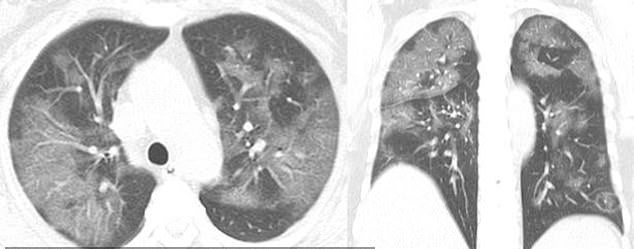

Die CT-Aufnahmen einer 54-jährigen Frau, die sich nach einer Reise nach Wuhan, China, das Coronavirus eingefangen hatte, zeigen teilweise die gleiche Füllung der Lufträume.

Auch bei der Frau wurde eine schwere Lungenentzündung diagnostiziert, die durch das Virus verursacht wurde, nachdem sie eine Woche lang an Fieber, Husten, Müdigkeit und Brustkorbstauung gelitten hatte.